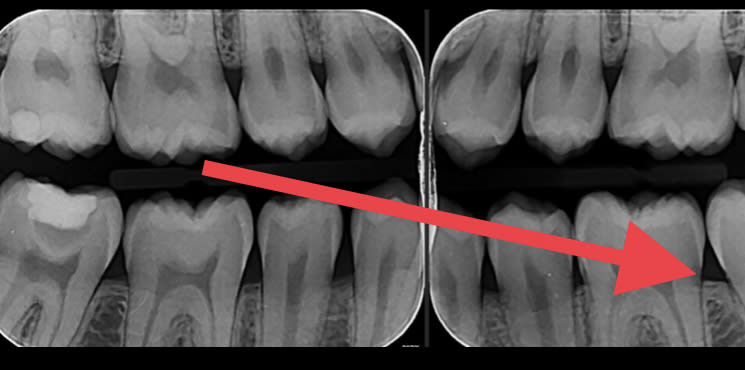

ci joint les radios, pour la 47 il ya une résine avec un fond de cavité

Ils veulent toujours une pano dans leur dossier : ils ont du en faire une ou en prescrire ne et ont vu la 47.

Que ferais tu en voyant une image de la 47? prendrais tu le risque d'envoyer le patient en Opex pendant des mois?

Explicite ton diagnostic avec des radios pour traiter de la stabilité clinique de ton coiffage pulpaire.

Meme si la 47 est a l'equilibre dentine tertaire-cavité-pulpe, la proximité pulpaire rend quad meme difficile la notion de stabilisation a long ou moyen terme.

Le dentiste de l'armée a jugé les risques potentiels que présenterait cette 47 .Il n'aurait pas du parler a proprement de carie, mais de risques non nuls de pulpite a moyen terme, pas top en opération.

Pas tres facile a classer, cette 47. Concretement, soyez honnetes, on vous dit "un an sur une ile deserte sans soins médicaux possibles" , vous vous feriez traiter endodontiquement cette 47 ou non avant de partir?

Le mec a certainement mis de la biodentine sur la 47 . Si la restauration supérieure n’est pas infiltrée, je ne vois pas pourquoi on s’amuserait à dépulper une dent asymptomatique

C est quoi ce fond de cavité qui est totalement radio-transparent ???

Clairement... C est a peine moins radio opaque que la dentine. La c est quand même très très radio clair...

Pour moi la c est de la biocarix... ;)

Non ça c est la projection de la convexité de la racine distale qui crée une zone radioclaire.

oui pourquoi pas. De toute façon ça ne coûte rien de démonter la restauration de 47 et de voir si il y a bien de la biocarix

Surtout qu après tu peux faire une jolie endocouronne.

Une belle endo + endocouronne et là il peut aller l esprit tranquille en opex avec un traitement a l apex.